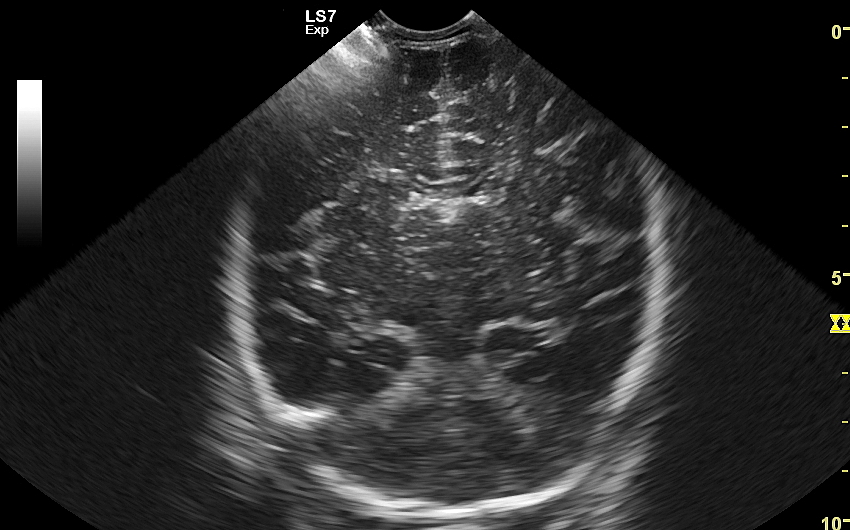

USG główki to podstawowa metoda diagnostyczna mózgu i struktur okołomózgowych u wcześniaków, noworodków i niemowląt. Badanie jest bezbolesne i nieryzykowne w porównaniu do rezonansu magnetycznego, podczas którego dziecko poddawane jest znieczuleniu ogólnemu. Przeprowadzenie szerokiego i szczegółowego badania USG główki jest możliwe aż do momentu zarośnięcia ciemiączka, czyli chrzęstnej struktury w pokrywie czaszki. Ze względu na cienką kość skroniową czaszki dziecka w późniejszym okresie możliwa jest wciąż częściowa ocena mózgowia w badaniu USG. Ambulatoryjne badanie USG przezciemiączkowe zwykle zalecane jest przez neonatologa, pediatrę lub neurologa dziecięcego w celu oceny mózgu wcześniaków, dzieci z małą masą urodzeniową, dzieci po epizodzie niedotlenienia lub krwawienia wewnątrzczaszkowego w trakcie porodu lub okresu noworodkowego, a także w przypadku wystąpienia drgawek, podejrzenia wady układu nerwowego, np. wodogłowia.

W USG główki dziecka oceniane są struktury wewnątrzczaszkowe, tj. mózg wraz z jego układem komór wewnętrznych, sploty naczyniówkowe, istota biała mózgu i obszary jąder podstawy mózgu, morfologia zakrętów i bruzd mózgowia, przestrzeń przymózgowa, a w trybach dopplerowskich wybrane naczynia tętnicze i żylne mózgu, w tym zatoki żylne. Oceniane są również cechy ciśnienia śródczaszkowego. W opisie badania podawane są również wymagane przez neurologa tzw. wskaźniki komorowe oraz wymiary wybranych struktur.

Badania USG mózgu dziecka wykonywane w warunkach szpitalnych i ambulatoryjnych różnią się od siebie charakterem stwierdzanych patologii. W szpitalu dominują ostre krwawienia wewnątrzczaszkowe oraz śródmózgowe. Z kolei najczęstszymi chorobami i stanami patologicznymi, które spotyka się w trakcie badania USG przezciemiączkowego przeprowadzanego w warunkach ambulatoryjnych są pozostałości po krwawieniach dokomorowych oraz śródmózgowych w postaci poszerzenia układu komorowego i torbieli; pozostałości po uszkodzeniach niedokrwiennych w postaci leukomalacji okołokomorowej i zaników mózgowych; poza tym zmiany pozapalne i wodogłowie wewnętrzne bądź zewnętrzne. Sporadycznie wykrywane są wady rozwojowe oraz guzy mózgu.